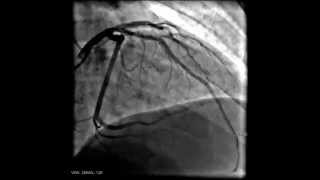

Коронарография и инфаркт миокарда

Коронарография: закрыта крупная артерия сердца (передняя межжелудочковая артерия. Правая артерия сужена, но проходима. Закрытая артерия ...

Angio Live